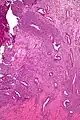

Micrograph of a uterine adenosarcoma showing a mitotically active malignant stroma and benign glands. H&E stain.

Uterine adenosarcoma have, by definition, a malignant stroma and benign glandular elements. The World Health Organization (WHO) criteria have a mitotic rate cut point; however, this is often disregarded, as bland-appearing tumours with a low mitotic rate are known to metastasize occasionally.[2]